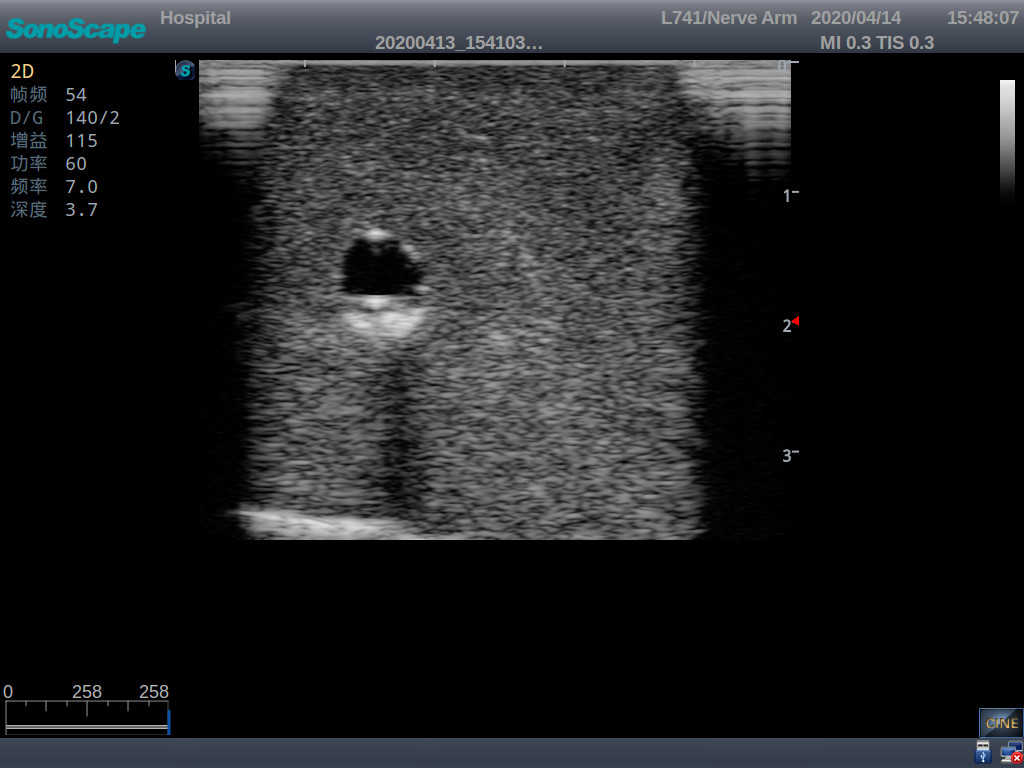

4)   When conducting vascular puncture, the piercing can be truly felt, and venous blood outflow can be seen

5)   Observe the guide wire marches

6)   Detect whether the catheter is properly placed